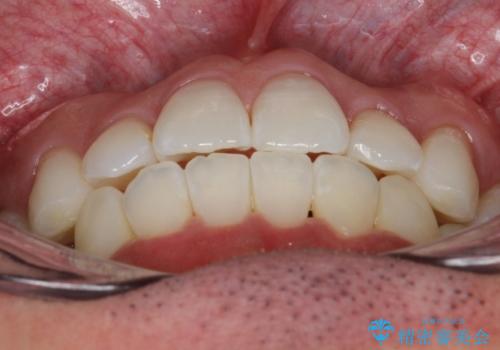

フルリンガル矯正 非抜歯でガタつきを整える

- 1年6ヶ月

- フルリンガルワイヤーによる非抜歯治療を計画しました。